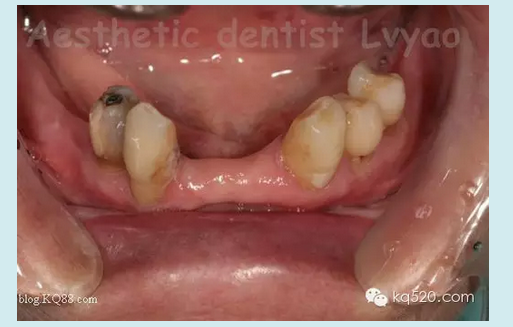

本病例在去年完成,患者是我的親人,現(xiàn)在修復(fù)體用的很好很舒適。患者上頜牙良好,下頜余留牙左下345良好,右下34有不同程度的牙槽骨吸收,右4松動(dòng)2度、右3松動(dòng)1度,臨床冠根比失調(diào)。原患者使用普通支架活動(dòng)義齒,現(xiàn)因基牙問題等因素導(dǎo)致使用不佳,以保存基牙的原則等因素,本人設(shè)計(jì)了套筒冠與栓體栓道式附著體聯(lián)合應(yīng)用的修復(fù)技術(shù)。有關(guān)文獻(xiàn)報(bào)道,對(duì)于患者牙列缺損 少量基牙伴牙槽骨吸收或牙周病,不宜固定修復(fù)又對(duì)美觀、功能、舒適要求高??刹捎锰淄补谂c栓體栓道式附著體修復(fù)技術(shù)聯(lián)合的方法,此方法充分利用了栓體栓道式附著體固位力強(qiáng),義齒清洗時(shí)仍可維持垂直距離以及其固位體隱蔽和套筒冠技術(shù)的良好的基牙保護(hù)性能及可以在垂直及水平方向都能提高義齒的固位和穩(wěn)定性等優(yōu)點(diǎn)。有學(xué)者研究調(diào)查,發(fā)現(xiàn)套筒冠與栓體栓道式附著體聯(lián)合應(yīng)用的修復(fù)技術(shù)具有美觀、舒適、固位穩(wěn)定性良好、咀嚼效率高、保存保護(hù)基牙等優(yōu)點(diǎn)。實(shí)驗(yàn)表明牙周病患者能較快地適應(yīng)套筒冠義齒,咀嚼功能有所提高;套筒冠義齒具有良好的夾板固定效果,顯著降低牙周病患牙的松動(dòng)度,顯著減小牙周病患牙的牙周袋深度。

此病例正是如此,套筒冠主要的作用是保存維持了嚴(yán)重牙槽骨吸收的右下34基牙,改善了原基牙的臨床冠根比,縮短臨床冠高度大大減輕了對(duì)基牙承受的牙合力等其他應(yīng)力,減緩了牙槽骨的吸收,維持了基牙的使用壽命,再利用栓體栓道式附著體幫助,應(yīng)力分布更為均勻,從而修復(fù)后達(dá)到了非常好的效果。說了那么多,還是看看病例照片吧:

修復(fù)前口內(nèi)影像